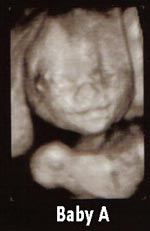

Yep - Baby A is me, Baby B is DH Image Attachment(s):

did anyone try to guess which one was what sex by the pics? I have to tell ya my guess would be A- Girl B-Boy . They dont look like the same sex to me. DO you know yet?

No but I have a strong feeling. Kind of does look like a girl right? Poor thing, I might be calling her a boy this whole time!!!

LOL...totally! I definately think Baby B's a boy

Are you trying to guess the sex of yours??? (BTW these were at 20 weeks - I have another sono next week I'll let you know if things change.)

Yeah he kind of looks like a little old man right?